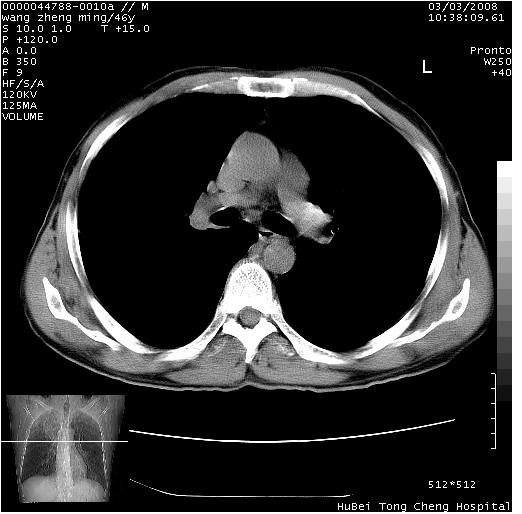

以下是引用卜一在2008-3-22 1:37:00的发言:[br]右肺实质性肿块,边缘不整,明显见毛刺征 分叶征及胸膜凹陷征,右上叶支气管明显变窄,远端散在的片状 斑片状实变影。另:左肺门较大肿块,支气管受累 变窄,远侧见阻塞性肺炎。纵隔内见肿大淋巴结。多考虑:右肺周围性肺癌伴左肺门 纵隔淋巴结转移!